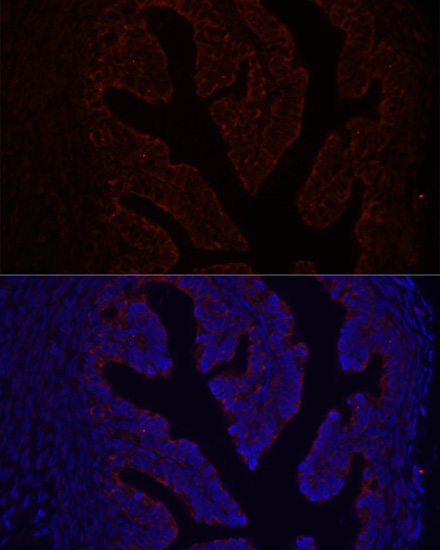

Immunofluorescence analysis of rat ovary using COL1A1 antibody.

Immunofluorescence analysis of human breast cancer using COL1A1 antibody.